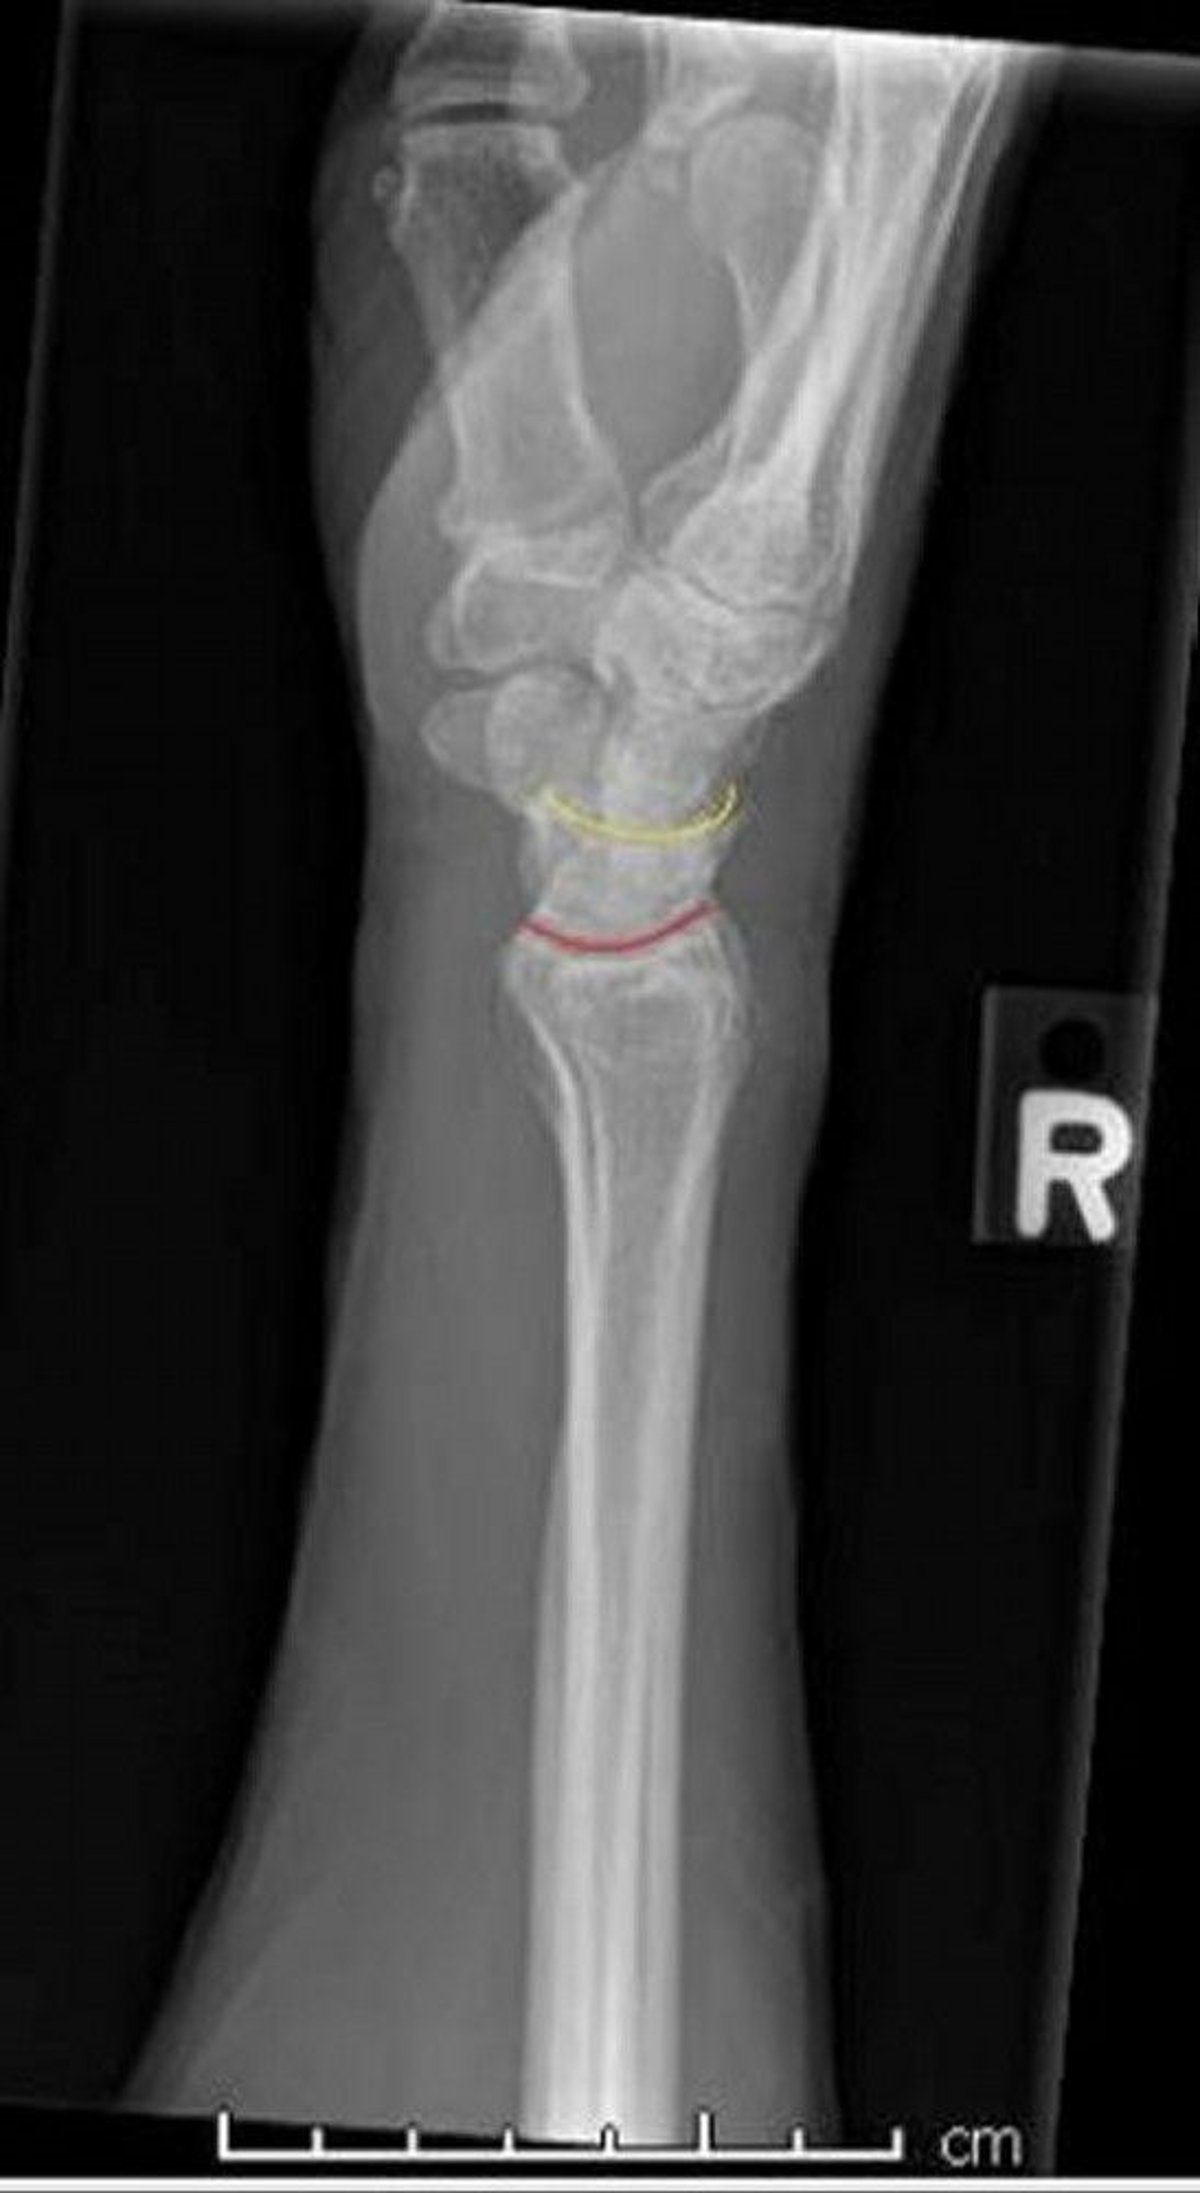

Normal Wrist: Lateral View

This lateral view of a normal wrist demonstrates the normal interface between the radius and lunate (red line) and the lunate and capitate (yellow line).

Image courtesy of Danielle Campagne, MD.